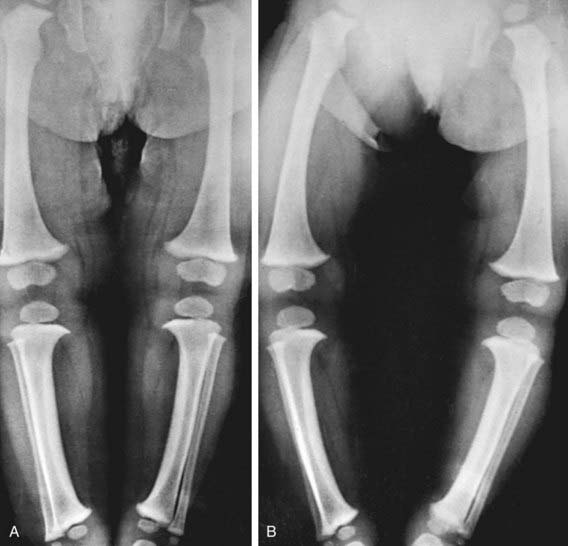

Physiologic bowleg is a common torsional combination that is secondary to normal in utero positioning (Fig. 667-8). Spontaneous resolution with normal growth and development can be anticipated. Persistence of varus beyond 2 yr of age may be pathologic. The different causes are metabolic bone disease (vitamin D deficiency, rickets, hypophosphatasia), asymmetric growth arrest (trauma, infection, tumor, Blount), bone dysplasia (dwarfism, metaphyseal dysplasia), and congenital and neuromuscular disorders (Table 667-1). It is prudent to differentiate physiologic bowing from Blount disease (Table 667-2). Physiologic bowing should also be differentiated from rickets and skeletal dysplasia. Rickets has classic bone changes with trumpeting widening and fraying of the metaphysis and widening of the physis (Chapter 48).

image

Figure 667-8 A, In recumbent position, tibia and femora are bowed but the legs do not appear bowed. B, In erect position during weight bearing and with ankles in apposition, the legs are bowed.

(From Slovis TL, editor: Caffey’s pediatric diagnostic imaging, ed 11, Philadelphia, 2008, Mosby.)